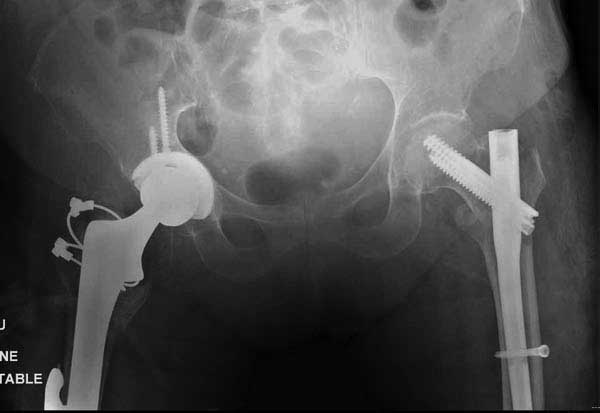

Третья операция-продолжения усилии “синьорами пэрами” по разрушению нормальной анатомии. Крест на головку! По видимому возраст позволяет биполярную конструкции, и при дефекте calcar пошли на обычный цементный. Ягодичные мышцы потеряли связь с вертелом, т.е. отсутствует верхний удержатель, и результат “a Big Screw Up!” Снимки вызывают головокружение!

Такие “чужие осложнения” встречаются у всех и представляю банальный случай, который шаг за шагом показано как перерос в более сложный процесс... Больная 70 лет, множественные ко-морбидности, чрезвертельный перелом первоначально фиксирован Гамма 3. Осложнение в течение 6 недель, ревизия тотальной артропластикой и во время установки ножки обнаружена трещина диафиза (17), из малого доступа фиксация алло-графтом.

Обычно после чрезвертельных переломов, за исключением молодых, у пожилых остается нестабильность при движении. Часто падают и после 3х мес. в результате падения обнаружен перипротезный перелом (22-23), который зафиксирован Синтез пластиной.

Повторно поступает после двух с половиной лет, где обнаруживается перелом на второй стороне. Немного сложно, но для фиксации выбрали Antegrade InterTan Smith Nephew Nail и с момента фиксации более 3х мес.